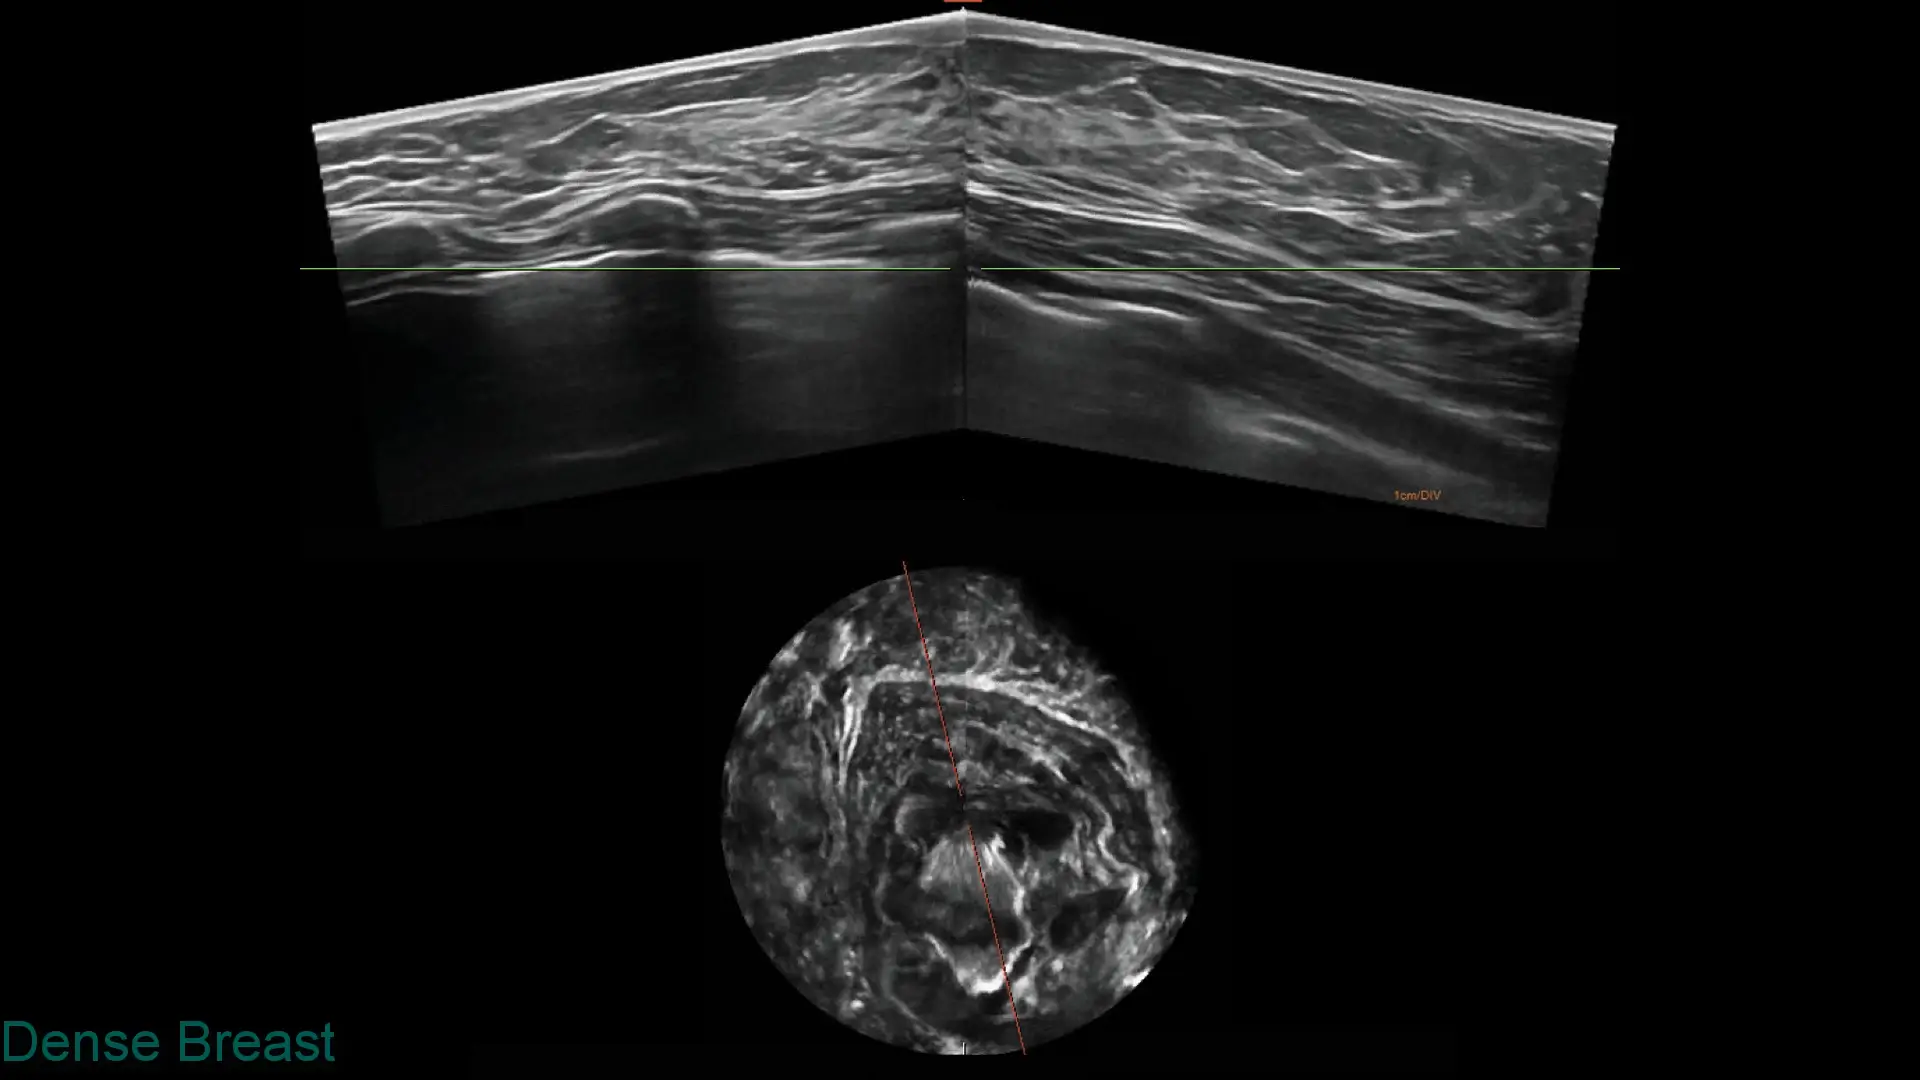

Explore clinical breast ultrasound images captured with SOFIA, showcasing various tissue types and conditions with exceptional clarity.